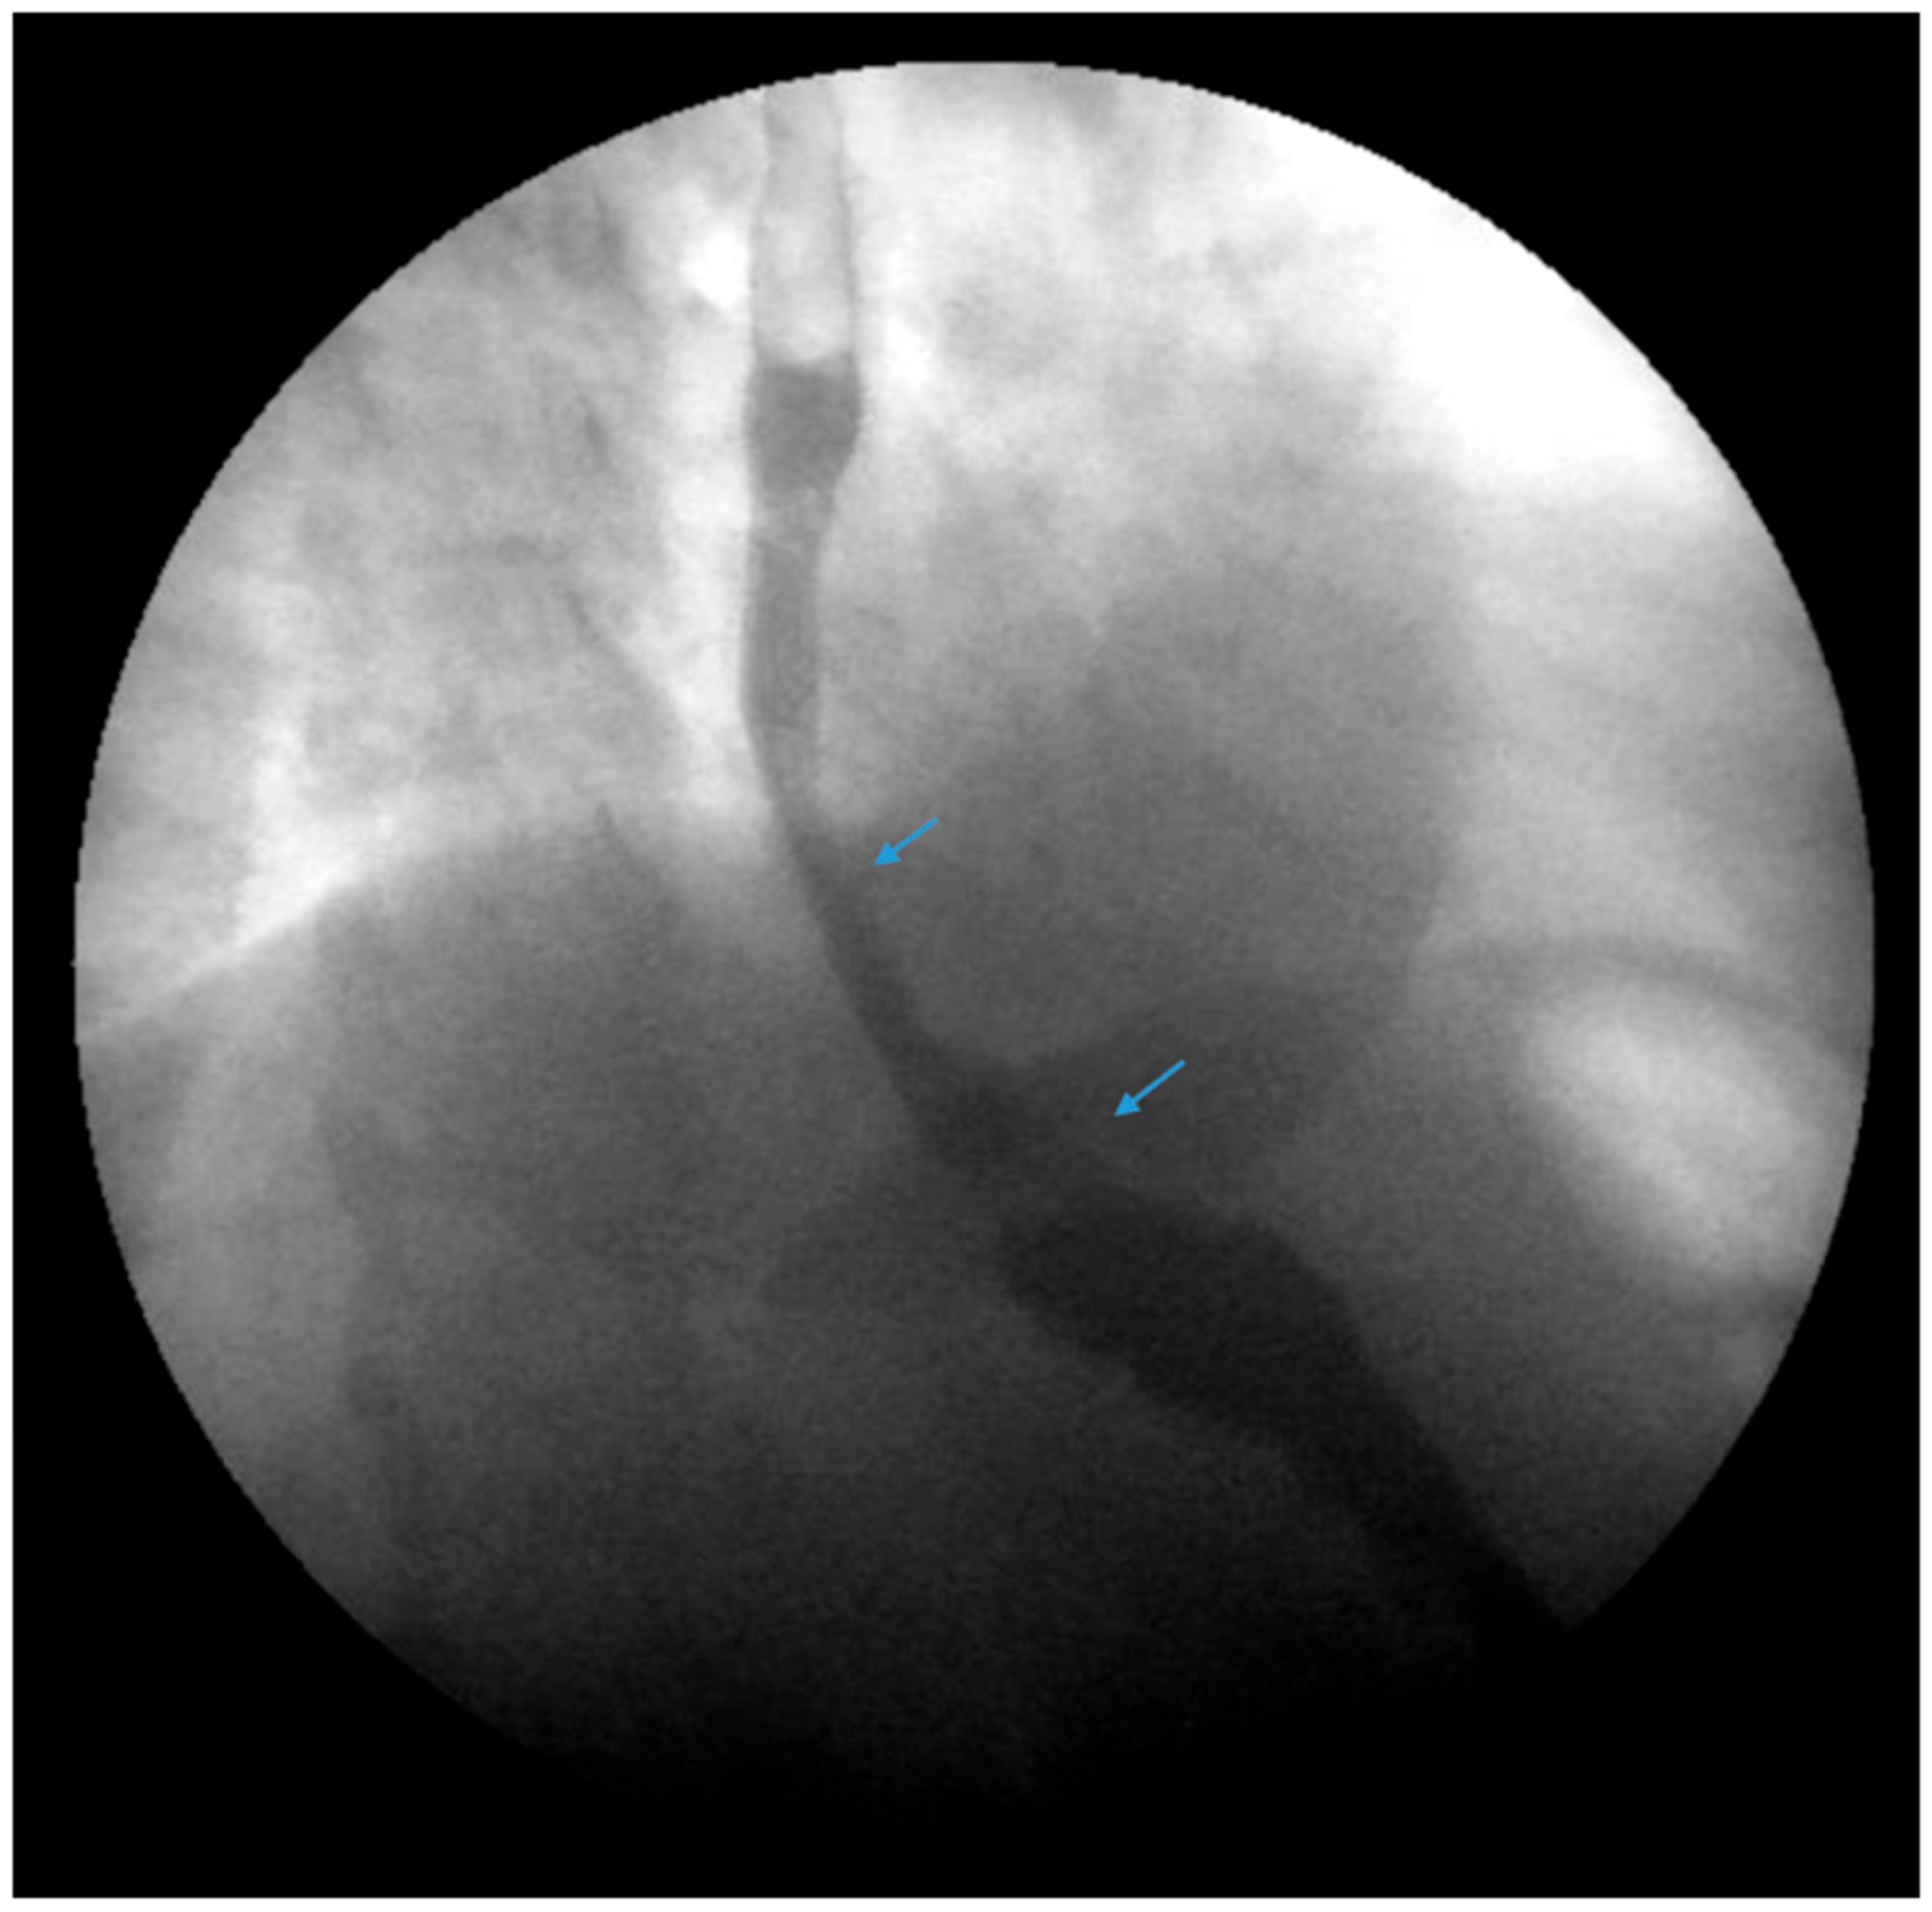

Figure 2.

An upper gastrointestinal series reveals a moderate, sliding type-one hiatal hernia (bottom arrow) in addition to gastroesophageal reflux disease (top arrow) in a patient with morbid obesity.

There are factors which may contribute to alleviating GERD after SG including weight loss leading to decreased abdominal pressure, reduced gastric volume and possibly accelerated gastric emptying [32,33]. In contrast, several pathophysiological mechanisms for de novo or increased GERD following SG have been described. Anatomic disruption of the antireflux barrier, including the esophagogastric junction, gastroesophageal flap valve, the angle of His, the gastric sling fibers and the fundus, may result in an increasing propensity for the reflux of gastric contents. Others discuss that caution must be made when positioning the staple line during SG in a manner that will preserve the antireflux barrier [34]. In contrast to RYGB, SG may be more likely to disrupt the angle of His and gastroesophageal junction attachments. There may be a functional impairment at the gastroesophageal junction such as with a hiatal hernia (Figure 1 and Figure 2). In one study, 37% of 181 morbidly obese patients were noted to have a hiatal hernia during preoperative work-up for bariatric surgery [35]. Repair of the hiatal hernia, if present, at the time of SG is recommended to reduce the risk of postoperative GERD although hiatal hernia repair may pose a challenge in patients with large hernias, especially those associated with esophagitis or Barrett’s esophagus [35,36].